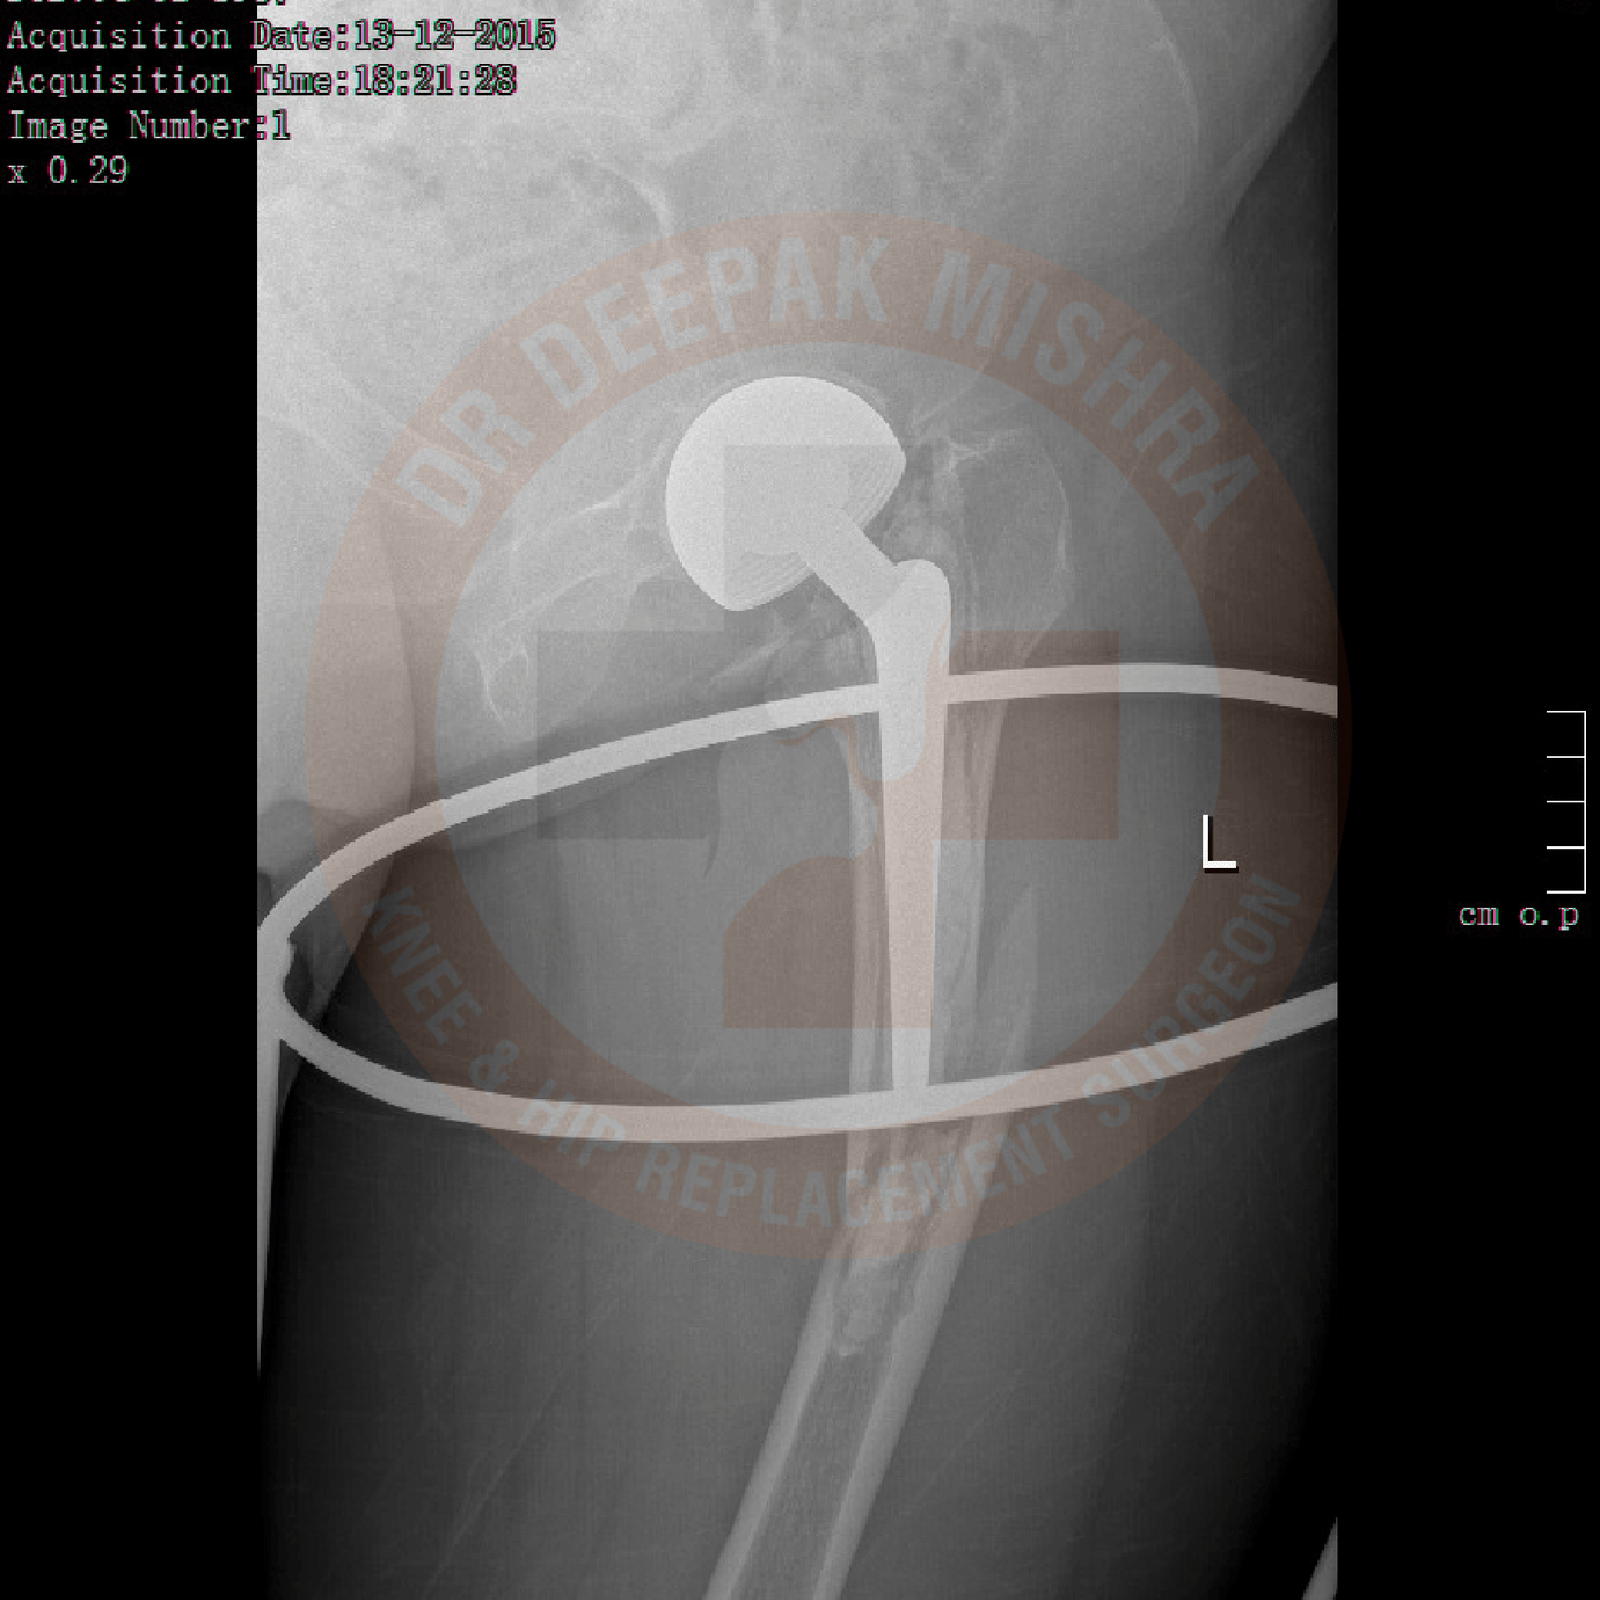

Total Hip Replacement implants mainly fall into two categories – cemented and uncemented. In cemented implants, antibiotic-laden polymethyl-methacrylate is used to fix the implant to the bone. In an uncemented implant, it directly fixes to the bone. Uncemented implants have a larger global acceptance today. Another major advancement occurred in the “bearing surface” between the acetabular and femoral implant. This is the surface on which hip joint moves after the surgery. Sir John Charlney introduced high-density polyethylene as bearing surface and it revolutionized the replacement surgery. Later, the metal-on-metal bearing was introduced in 1960s. Failure rates were higher than acceptable with these two bearing surfaces. Presently used bearings are highly crossed-linked polyethylene with cobalt chrome metal, highly crossed-linked polyethylene with delta ceramic and delta ceramic on delta ceramic. All three have proven past record and used worldwide. There is a general consensus to use Ceramic on Ceramic in younger patients and in those older patients who are physically active.

In total hip replacement surgery, we remove the damaged femoral head (ball) and cartilage of the acetabulum (cup) and replace it with metal implants. During the surgery, size of the acetabulum and femoral head are measured to provide optimized size of the implant.

Yes, it is very successful. The more and more young population is undergoing Total Hip Replacement surgery across globe now-a-days. This has been made possible due to –

(a) better surgical technique

(b) advancement in implant design

(c) improvement in metal quality

(d) improvement in ball-socket material (e.g, ceramic)